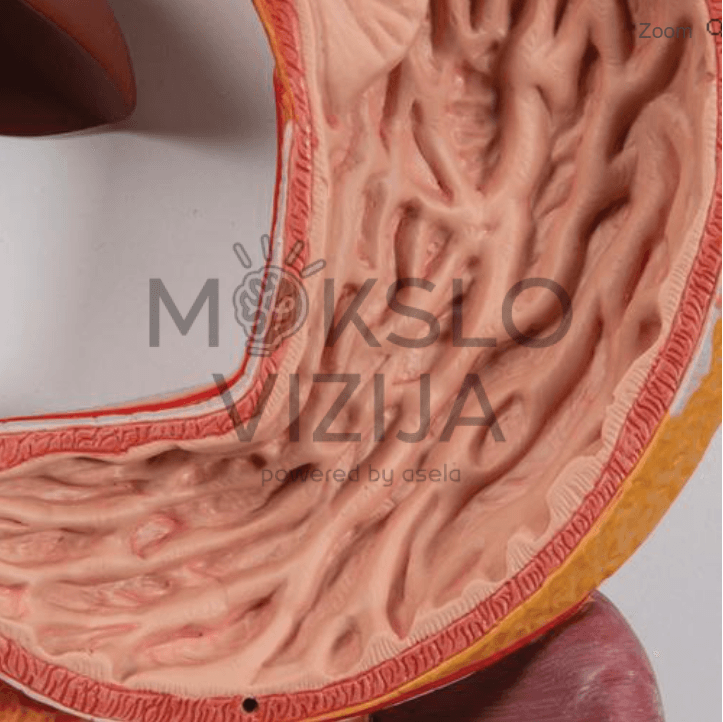

Dešinėje modelio pusėje esantis kepenų ir skrandžio segmentas išimamas, todėl galima apžiūrėti vidaus organų tarpusavio santykį iš kelių kampų. Tokia konstrukcija leidžia lengviau paaiškinti virškinimo proceso eigą ir vidaus organų funkcijas.

- Tiksli žmogaus virškinimo sistemos anatomija nuo burnos iki tiesiosios žarnos

- Nuimamos dalys: kepenys su skrandžio dalimi, atidaromas skrandis

- Matomi vidaus organų paviršiai ir struktūros